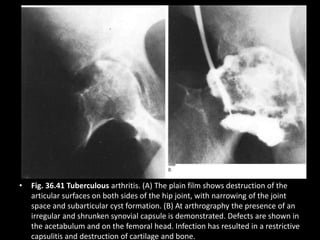

• Fig. 36.41 Tuberculous arthritis. (A) The plain film shows destruction of the

articular surfaces on both sides of the hip joint, with narrowing of the joint

space and subarticular cyst formation. (B) At arthrography the presence of an

irregular and shrunken synovial capsule is demonstrated. Defects are shown in

the acetabulum and on the femoral head. Infection has resulted in a restrictive

capsulitis and destruction of cartilage and bone.

• Fig. 36.41Tuberculous arthritis. (A) The plain film shows destruction of the articular surfaces on both sides of the hip joint, with narrowing of the joint space and subarticular cyst formation. (B) At arthrography the presence of an irregular and shrunken synovial capsule is demonstrated. Defects are shown in the acetabulum and on the femoral head. Infection has resulted in a restrictive capsulitis and destruction of cartilage and bone.